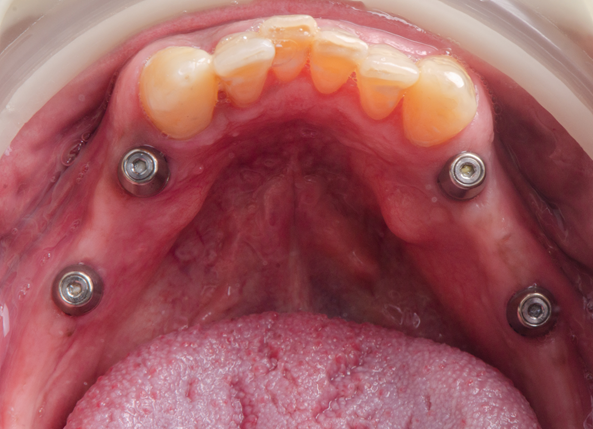

A mandíbula do paciente apresentava-se atrófica e tinha ausência dos dentes 34, 35, 36, 37, 44, 45, 46 e 47. Foi então planejada a inserção de quatro implantes e a confecção de pônticos sobre implante. Todo o planejamento foi realizado utilizando o software Exocad, que também foi empregado para a confecção da guia cirúrgica, garantindo a angulação adequada e o cumprimento dos pré-requisitos do implante, além das distâncias de segurança.

Conforme o planejamento, os implantes foram posicionados nas posições correspondentes aos dentes 34, 36, 44 e 46. Foram utilizados três implantes da Implacil De Bortoli, especificamente o Due Cone – Maestro CM Pilar Digital 4.5 Ø 3,5x9mm nas regiões dos dentes 34, 36 e 44, e o implante 3,5x7mm na região do dente 46, devido a proximidade com o canal mandibular.

Após toda essa etapa preliminar, inicia-se o momento cirúrgico com a anestesia e a fixação da guia cirúrgica com dois pinos de fixação ancorados na região vestibular dos pré-molares.

A cirurgia foi realizada por meio da técnica flapless, começando com a utilização da fresa lança helicoidal associada ao guide, seguida pela fresa cônica de 3mm, de acordo com as especificações técnicas do implante. Após a verificação com sonda periodontal, a fresagem foi continuada com a fresa cônica de 3,5mm, respeitando o comprimento do implante e a margem gengival, antes da instalação dos implantes e do torque manual.

A guia cirúrgica foi removida, o torque foi conferido e foi colocado o tapa-implante. Associado a isso, também foi realizada a verificação dos implantes por meio de radiografia periapical.

Posteriormente, após o acompanhamento e o tempo pré-determinado, foi realizada a reabertura e a colocação de cicatrizador a fim de realizar a readequação dos tecidos moles peri-implantares. Nesta sessão, as demais etapas clínicas propostas já estavam finalizadas.

Por fim, o tratamento finalizou com a carga precoce dos implantes que culminam na instalação dos pônticos de zircônia sobre os implantes.